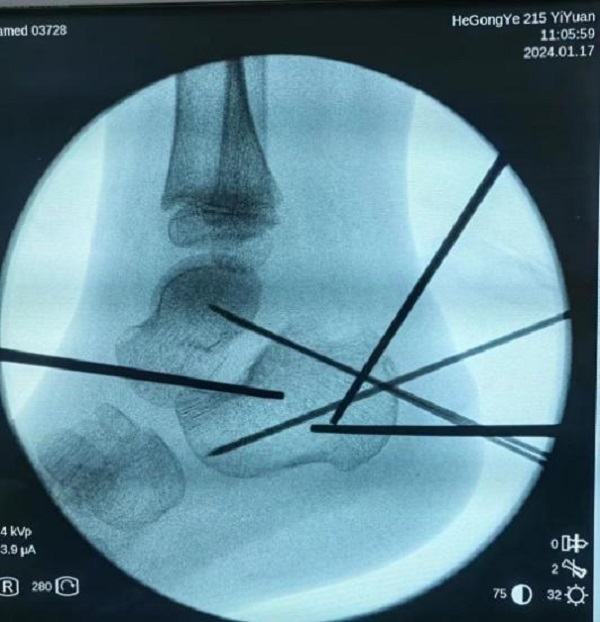

病情研判过程中,考虑到孩子年龄尚小,必须以最小的创伤完成治疗,用最快的速度让孩子恢复。宋强主任多频次组织团队阅片讨论,探究最佳诊疗方案。讨论认为,此例跟骨骨折涉及关节面,并且出现关节面塌陷,手术指征非常明确。在与家属充分沟通取得信任和支持后,宋强主任团队决定为小铎施行踝关节镜下微创手术治疗。考虑到儿童的病情进展较快,伤后第3天,手术便紧急开展。

手术过程中,关节镜从微小的窗口进入患儿体内探查,将病灶部位情形以最大视角、最佳角度呈现在监视画面中。关节镜直视下发现,关节面分离移位的程度远超影像资料提供的片面数据,手术的难度与复杂程度比预想的要大很多。在关节镜的辅助下,宋强主任团队专注谨慎,每一个步骤、每一次下刀都力争分毫无差,凭借多年累积的专业经验和技术水平,在约一个半小时的精细操作后,关节成功复位,手术精准且顺利的完成。

复位后,达到满意效果

关节面成功复位,创伤也很小

“手术很成功,术中通过利用踝关节镜,孩子的创伤很小,仅有两个4mm的切口,愈合更快,避免了大切口手术可能导致的伤口感染、瘢痕挛缩、皮瓣坏死等风险。大约4周以后,孩子就能下地,经过一段时间的康复休养,就可以和之前一样正常生活上学,脚部的功能不会受到影响。”宋强主任向患儿家属科普。